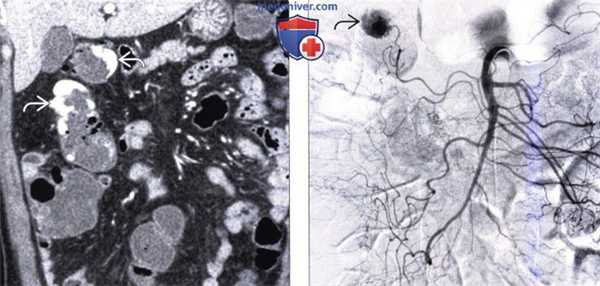

(а) На рентгенограмме ободочной кишки визуализируются утолщенные складки, наличие которых обусловлено утолщением циркулярной мышцы (стрелки) — вторичные изменения по отношению к укорочению и утолщению продольной ленты ободочной кишки. Дивертикулы (указатели) представляют собой мешковидные выпячивания стенки кишки между волокнами циркулярного мышечного слоя.

(б) На КТ дивертикулы (указатели) выглядят как мелкие выпячивания, распространяющиеся в жировую клетчатку, окружающую ободочную кишку; содержащие газ, контрастное вещество или каловые массы. Определяется циркулярное сужение пораженной стенки ободочной кишки в виде «зубьев пилы» (myochosis).

(в, г) На фотографиях, выполненных при колоноскопии, визуализируются множественные входные отверстия дивертикулов (указатели). Дивертикулы часто могут заполняться уплотненными каловыми массами и плохо опустошаются. Дивертикулиты: типичные КТ и УЗ-признаки.